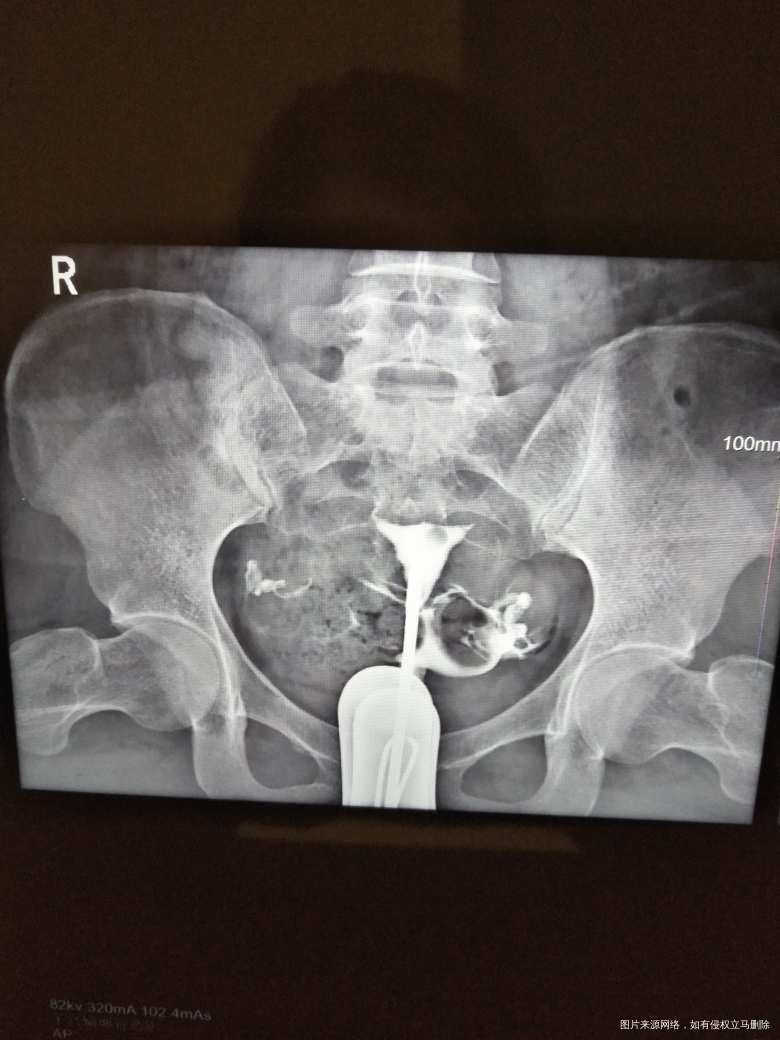

帮我分析下,红色圈这边是什么情况,另一什么情况?片子是不是方向是反的?红色这边是身体哪边的输卵管?谢谢,麻烦医生了

你好,那是右边。图片有写R。造影会有报告单,就会写明造影结果。祝你好孕。如果我的建议对您有帮助,请记得选择采纳

你好!根据图片显示右侧不通畅

你好!根据图片显示右侧输卵管近端不通畅。

你好,根据图片显示右侧输卵管近端不通畅。